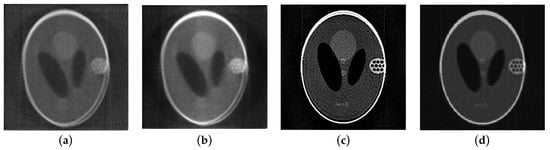

3.1. Numerical Phantom Experiments